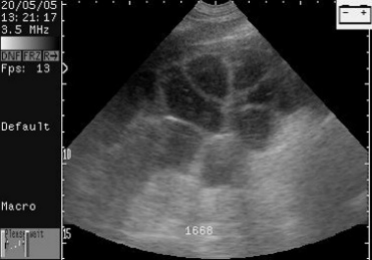

有囊肿的空怀母猪。这头母猪永远不会怀孕。

Scan of empty sow with cysts. This sow will never be pregnant.

有一个副卵巢囊肿的母猪。这头母猪能够怀孕。

Scanning of sow with one paraovarian cyst. This sow could get pregnant.

扫描配种第24天的母猪,大的胚胎囊可以很容易的看到。

Scans day 24. Large embryos bladders which are easy to see.